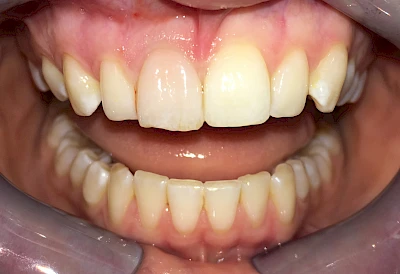

Verfärbungen an Zähnen können außen aufgelagert oder im Zahn eingelagert sein.

Von innen (endogen)

- Durch Blutabbauprodukte, weil der Zahnnerv abgestorben (einzelner Zahn, dunkel-flächig)

Ist ein einzelner Zahn deutlich dunkler als die Nachbarzähne kann das ein Zeichen sein, dass der Nerv abgestorben ist. Unter Umständen wurde bereits eine Wurzelkanalbehandlung vom Zahnarzt durchgeführt. Eine Abklärung durch den Zahnarzt ist in jedem Fall sinnvoll.